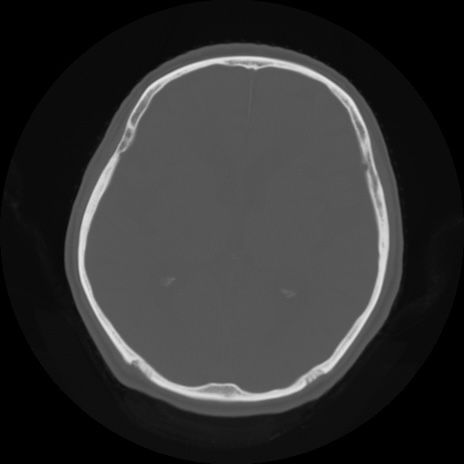

【頭部】症例5 CT(横断像)

【症例】80歳代 男性

【主訴】頭部打撲

【現病歴】外出先で椅子から立ち上がる際に、つまづいて後方へ転倒し受傷。転倒時に意識はあった。

【身体所見】BP 217/71、HR 96、JCS1-1、 難聴あり、顔色良好、右後頭部に擦過創あり。神経学的異常なし。

症例5の画像所見と診断は?